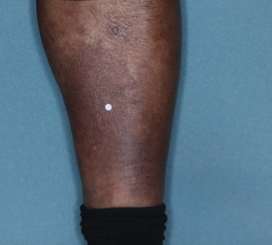

52 YO MALE - calf2

BASELINE

(IGA* = 3, NRS† = 5.86, BSA = 3.5%)

WEEK 2

(IGA = 2, NRS = 1.57, BSA = 1.75%)

WEEK 8

(IGA = 0, NRS = 0, BSA = 0%)

Actual clinical trial participant. Individual results may vary.